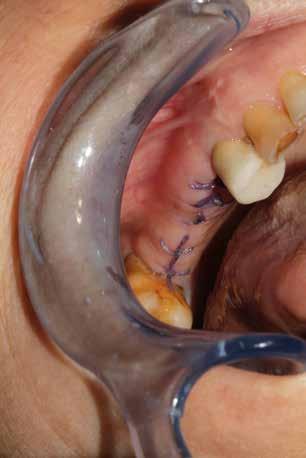

In ultimo, ha grande importanza anche il momento della sutura, la scelta dell’ago, del filo e la tecnica di legatura dei nodi (fatti alla giusta distanza gli uni dagli altri e con la giusta tensione); la riuscita dell’intervento dipende anche dalla qualità con cui vengono riavvicinati i lembi in modo da non ischemizzarne o danneggiarne i bordi. (Figg. 9-14)

Per ottenere una buona guarigione in tempi fisiologici è importante iniziare l’intervento chirurgico nell’ottica del massimo rispetto dei tessuti. Questo obiettivo può essere raggiunto minimizzando l’estensione dell’incisione ed esercitando una divaricazione dei lembi sufficiente a garantire visuale libera al chirurgo. Per la preparazione del sito implantare utilizzare la fresatura a bassi giri garantisce un minor impatto stressante sul tessuto osseo. Per aiutare la riparazione sono fondamentali due fattori: l’impiego degli emocomponenti e una buona tecnica di sutura. Questo percorso consente di ottenere un sigillo di qualità già a 7 giorni dall’intervento.